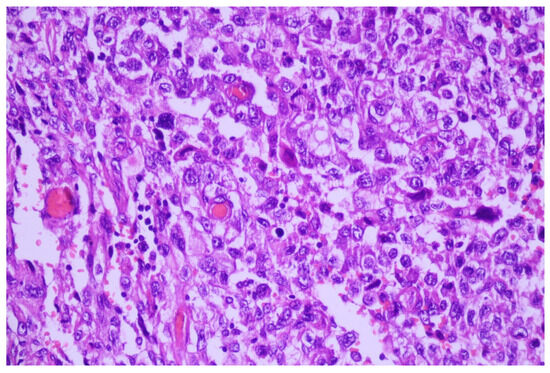

3.1. Case No. 1

3.2. Case No. 2

3.3. Case No. 3

3.4. Case No. 4